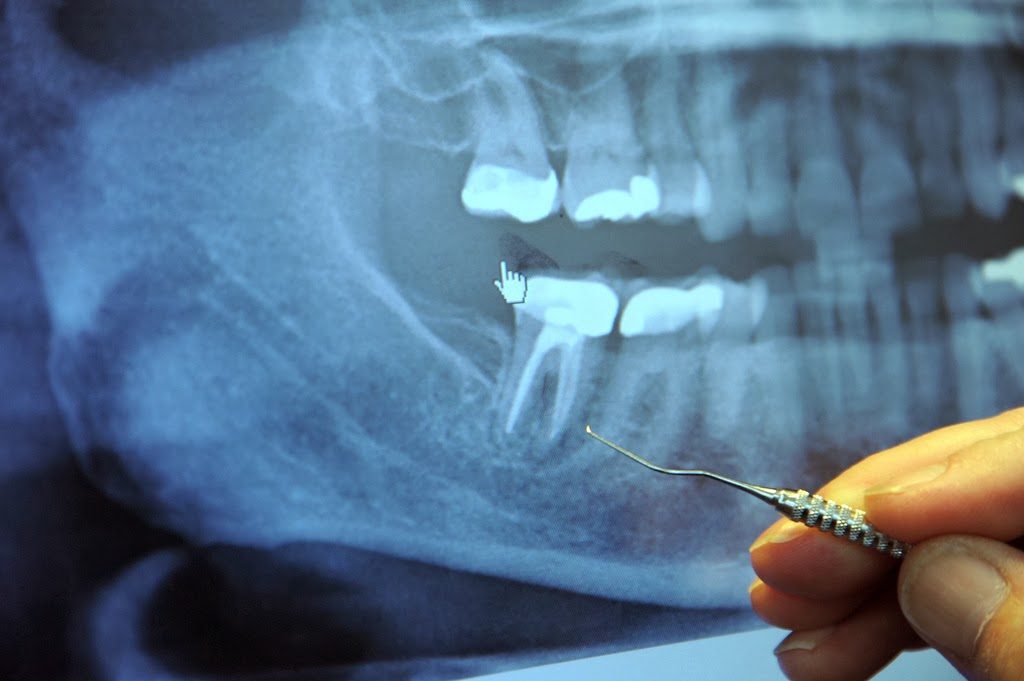

In the middle of each tooth is the pulp chamber, a soft living inner structure that houses blood vessels and nerves. Surrounding the pulp chamber is the dentin, which is made of living cells that secrete a hard mineral substance. The outermost and hardest layer of your tooth is the white enamel, which encases the dentin.

The roots of each tooth descend into your jawbone and are held in place by the periodontal ligament. In dental school, dentists are taught that each tooth has one to four major canals. However, there are accessory canals that are never mentioned. Literally miles of them!

Just as your body has large blood vessels that branch down into very small capillaries, each of your teeth has a maze of very tiny tubules that, if stretched out, would extend for three miles. Weston Price identified as many as 75 separate accessory canals in a single central incisor (front tooth). For a more detailed explanation, refer to an article by Hal Huggins, DDS, MS, on the Weston A. Price Foundation website.iii (These images are borrowed from the Huggins article.)

When a dentist performs a root canal, he or she hollows out the tooth, then fills the hollow chamber with a substance (called guttapercha), which cuts off the tooth from its blood supply, so fluid can no longer circulate through the tooth. But the maze of tiny tubules remains. And bacteria, cut off from their food supply, hide out in these tunnels where they are remarkably safe from antibiotics and your own body’s immune defenses.

No amount of sterilization has been found effective in reaching these tubules — and just about every single root-canaled tooth has been found colonized by these bacteria, especially around the apex and in the periodontal ligament. Oftentimes, the infection extends down into the jawbone where it creates cavitations — areas of necrotic tissue in the jawbone itself.